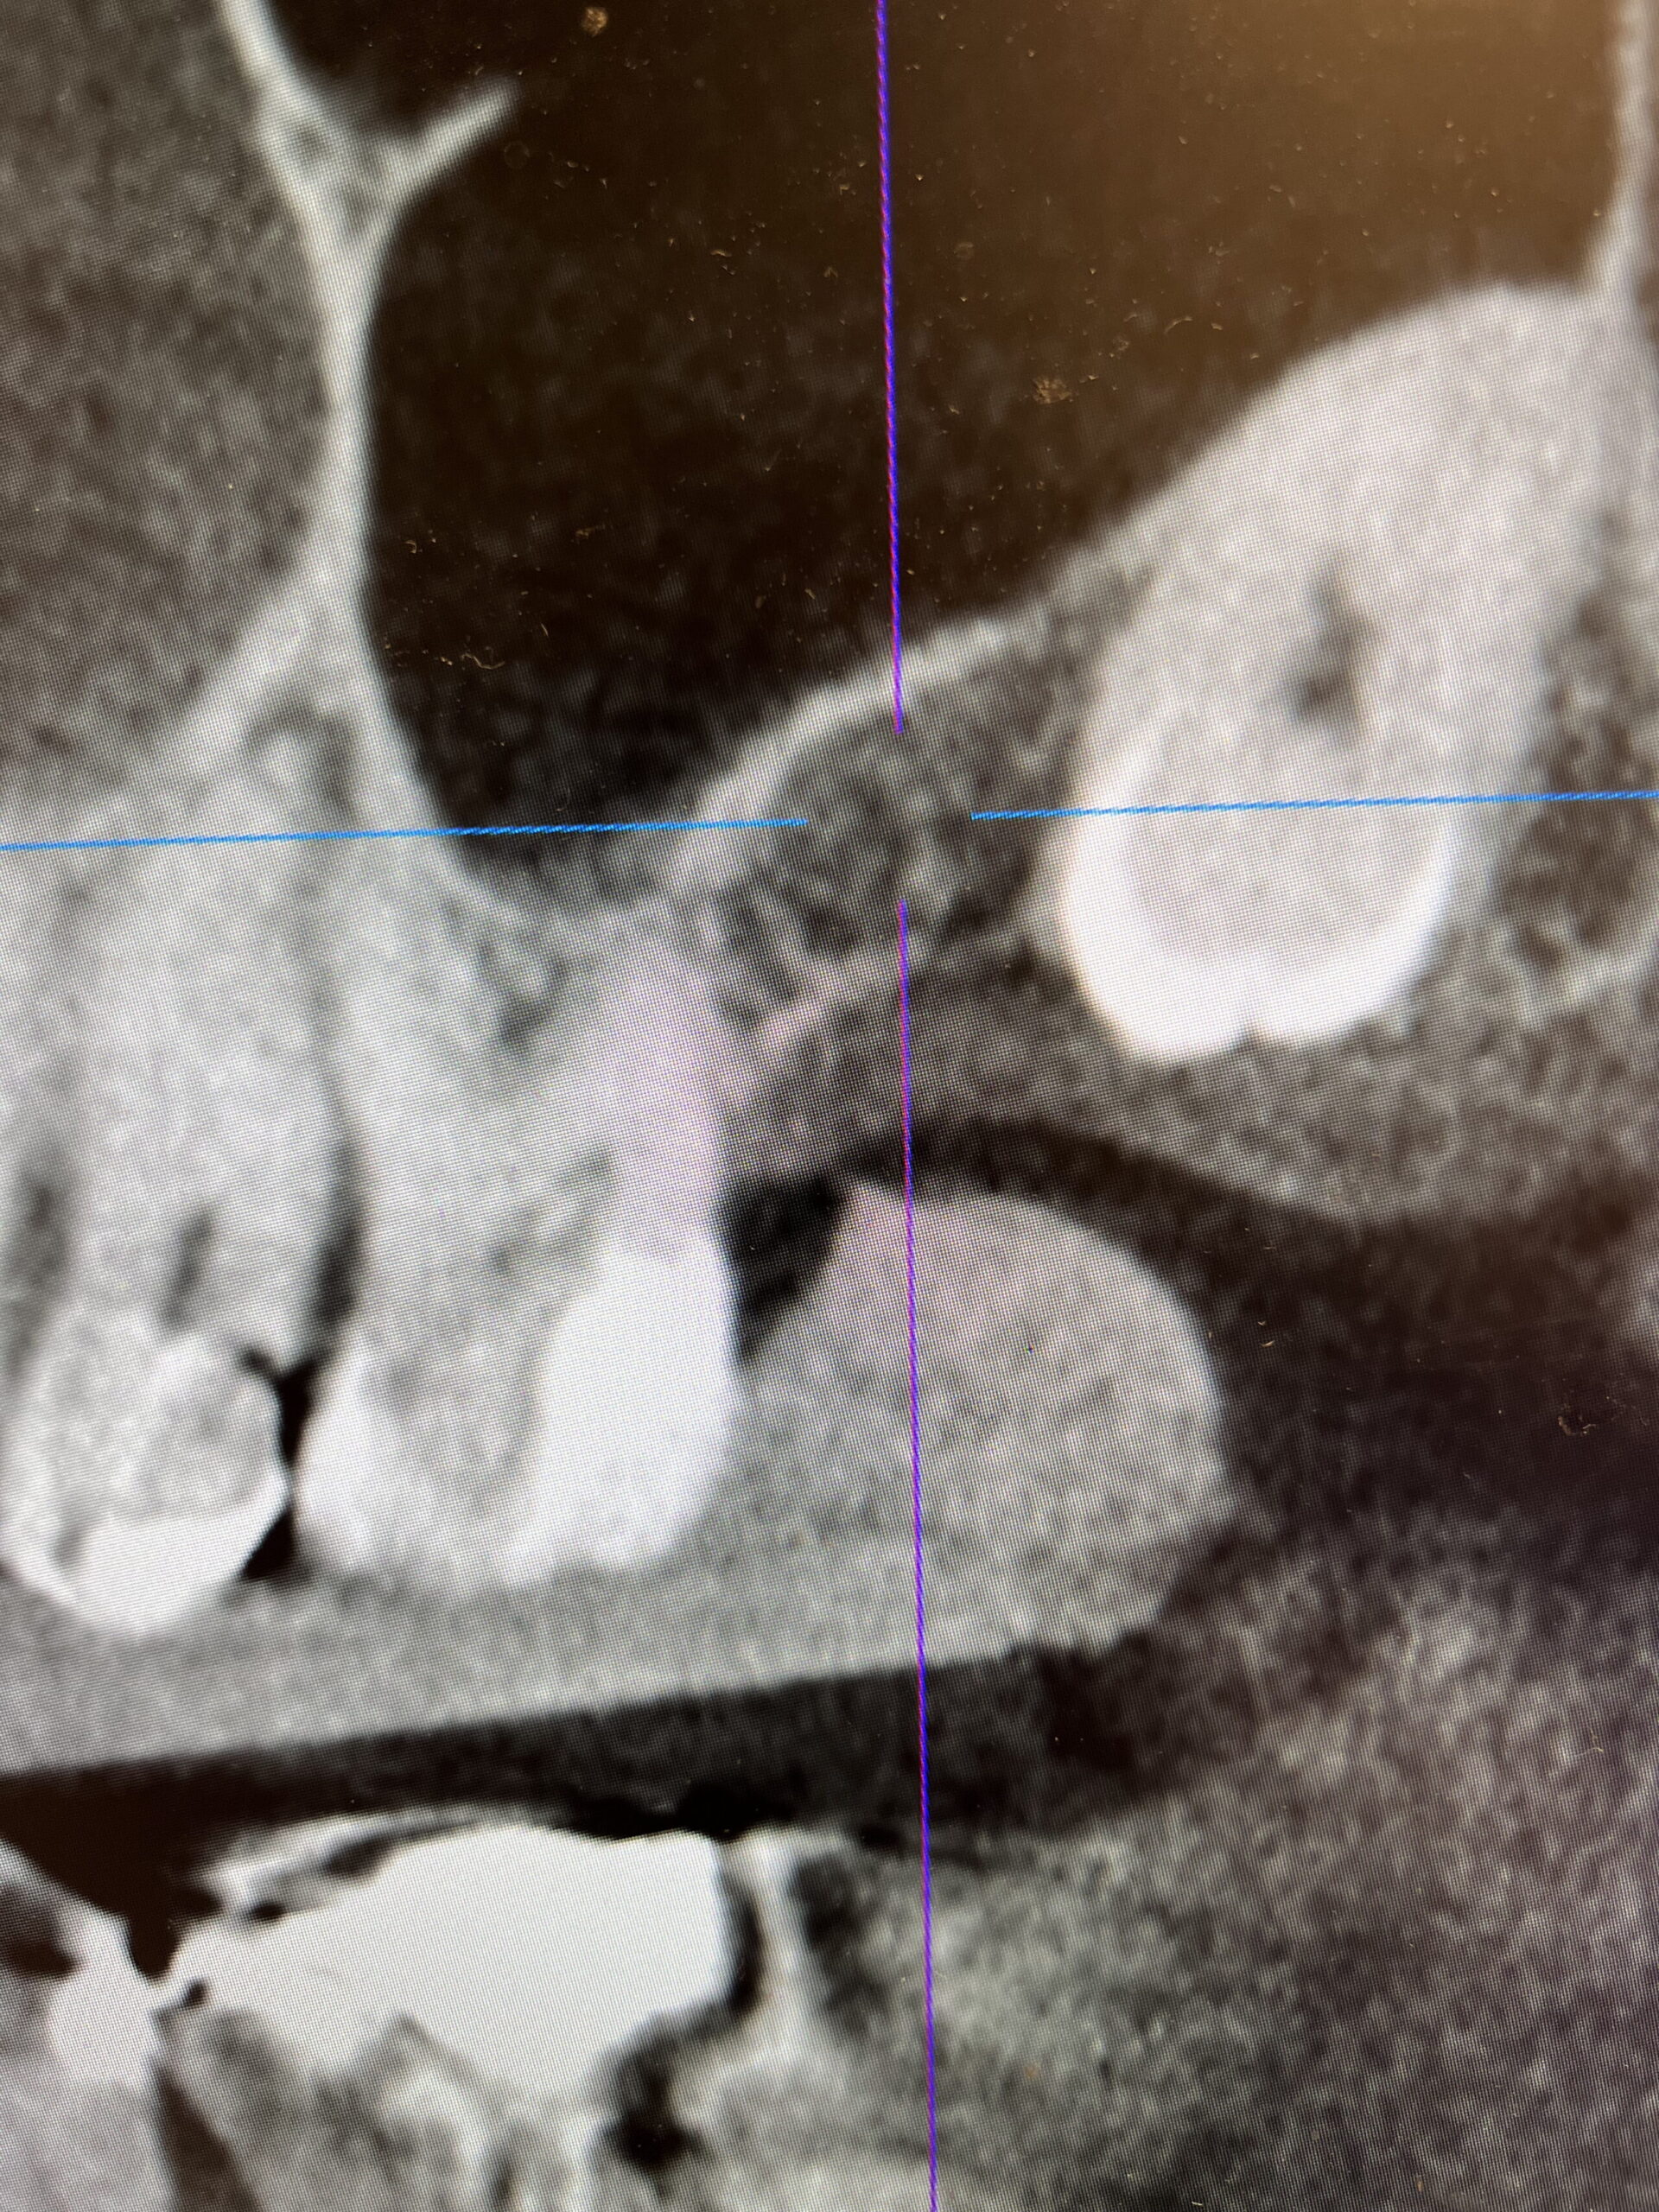

インプラント治療においてはサージカルガイドを活用しています。サージカルガイドは、歯科用CTと口腔内の高精度スキャンによって得たデータをもとに作成される補助ツールのことです。上顎や下顎の形状に合わせたU字型やV字型の形をしており、歯茎の上にフィットするように設計されています。サージカルガイドを用いれば、事前のシミュレーション通りの位置・角度・深さにインプラントを埋入できます。

コンピューターを使用し、嚙み合わせでベストな位置へインプラントを埋入する計画、シミュレーションを行います。

インプラントが下顎管と呼ばれる血管と神経が入った管に当たらないように調整します。

隣の歯の根っこにも当たらないように確認、調整を行います。

歯科用のCTは顎の骨の密度、神経や血管の配置などを立体的に把握できる装置です。通常のデジタルレントゲンでは3Dデータを得ることはできません。そのため、インプラント治療の精度を高めるうえでは、歯科用CTの活用は必要不可欠です。また、一般の医科用CTと比べて歯科用CTは被曝量が少なく、撮影時間も20秒ほどなので患者様への負担も大幅に軽減されます。